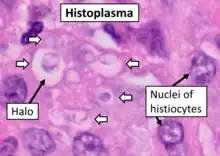

Histopathology of Histoplasma capsulatum, H&E stain, showing organisms surrounded by halos, in a granuloma of epithelioid histiocytes.

Histopathology of Histoplasma capsulatum, H&E stain, showing organisms surrounded by halos, in a granuloma of epithelioid histiocytes. Histopathology of Histoplasma capsulatum, GMS stain, showing narrow budding yeast